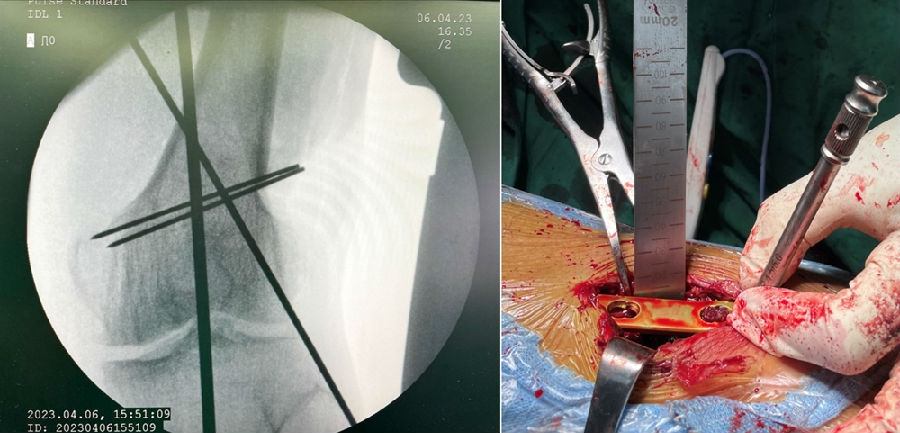

术后影像

患者二,女性,膝外翻,膝外侧疼痛。通过做畸形分析后发现,该患者同时存在股骨侧畸形、胫骨侧畸形和关节内畸形(LDFA=82°,MPTA=104°,JLCA=6°)。

对于这类病人如何进行术前设计的关键点就在于目标力线应如何设计。要在骨性截骨的时候纠正骨性畸形,关节内畸形要通过关节内的方法解决。因为JLCA不平行,所以要同时画股骨侧关节线和胫骨侧关节线,并垂直于股骨侧关节线做出股骨侧目标力线,垂直于胫骨侧关节线做出胫骨侧目标力线。

根据各自目标力线,分别计算股骨内侧闭合和胫骨内侧闭合角度。

此患者股骨内侧闭合6°,经股内侧闭合13°。